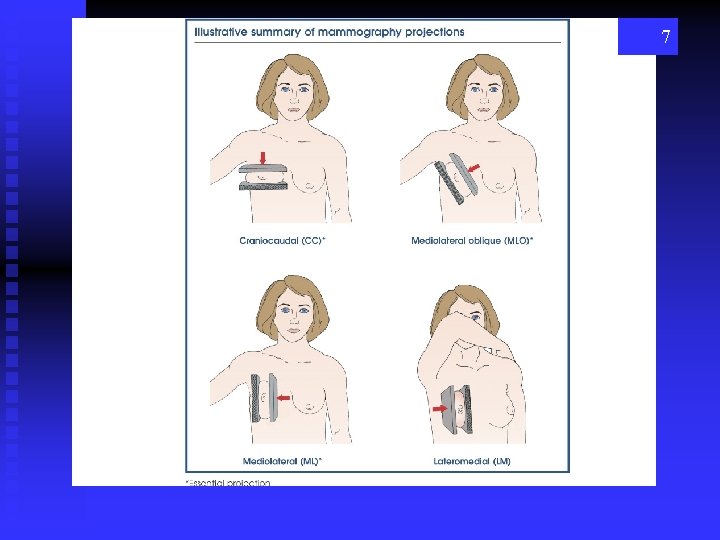

POSITIONING Routine Images aka “screening mammo” (not screaming) n. CC - cranio caudad n. MLO – mediolateral oblique 6

7